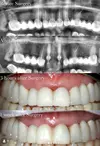

Zirconium Applications

Implant Treatment

Porcelain Applications

Laminate Veneer